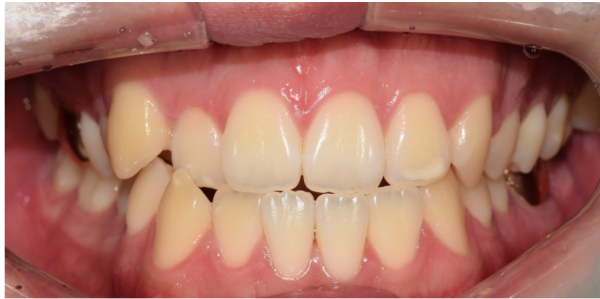

이 환자분의 치아 사진입니다.

정면에서 보았을대 치아가 정상적으로 겹치는게 아니라

맞 닿아 있습니다.' 이러한 치아를 엣지 투 엣지(edge to edge)라고 합니다.

This is a picture of your teeth.

He saw it from the front. His teeth didn't overlap normally

It's touching.' These teeth are called edge to edge.